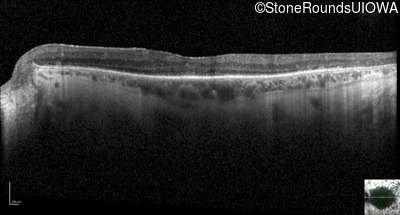

Optical Coherence Tomography - Right - 20/25 +1

Exemplar / OCT Stack